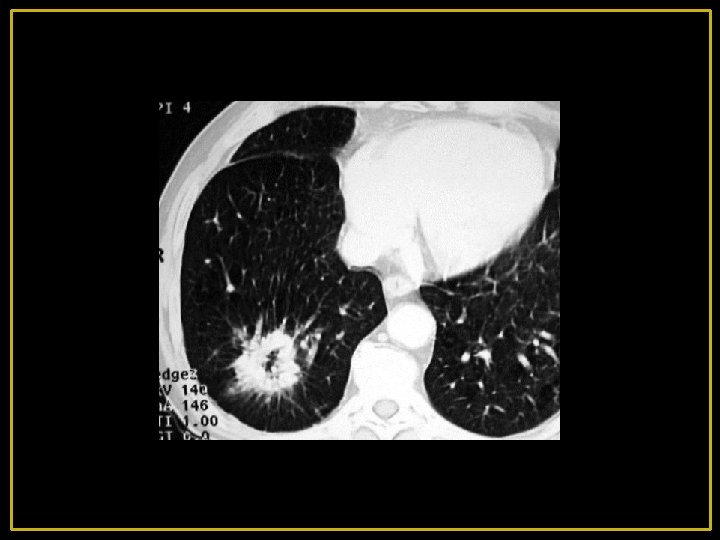

2 - malignes: Le cancer broncho-pulmonaire excavé: - Excavation dans 1/6 des cas environ (++ épidermoïde) - Peut se voir dans les tumeurs centrales ou périphériques - Elle peut contenir un niveau hydro-aérique - La paroi cavitaire est généralement épaisse et de contours irréguliers - Une image en « grelot » est possible par détachement d'un fragment de tissu nécrosé